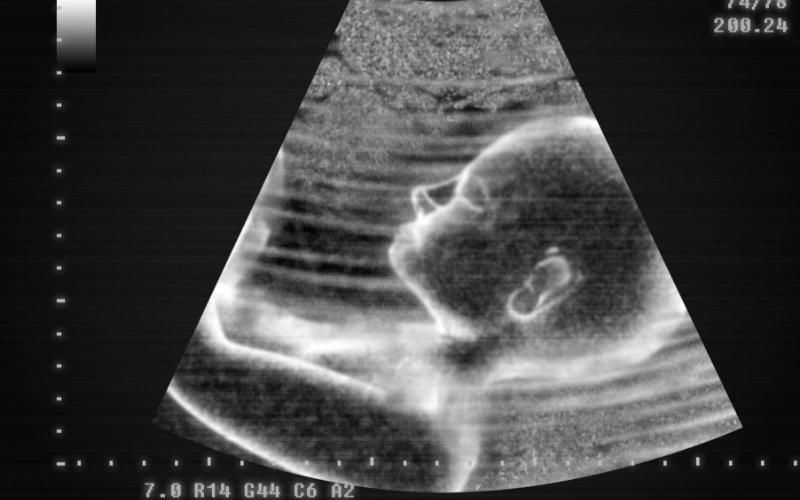

Tình trạng này thường xảy ra nghiêm trọng ở thời kỳ tam cá nguyệt thứ nhất. Tuy nhiên, vẫn có một số bà bầu tháng thứ 7 bị nôn, thậm chí kéo dài tới khi sinh con. Theo các chuyên gia, nguyên nhân khiến bà bầu tháng thứ 7 bị chóng mặt buồn nôn thường là do:

Thai nhi phát triển nhanh trong tháng 7 thai kỳ có thể làm cho mẹ bầu 7 tháng buồn nôn. Nguyên nhân dẫn đến điều này là do tử cung to và gây áp lực lên phần ổ bụng như ruột và dạ dày của mẹ bầu. Khi phần ổ bụng bị chèn ép, quá trình thực phẩm đi vào ruột non sẽ diễn ra chậm hơn và phần lớn thức ăn sẽ bị ứ trệ ở dạ dày, làm cho mẹ bị buồn nôn, khó tiêu hoặc ợ nóng.